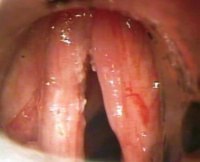

• Непрямая или эндоскопическая ларингоскопия. Ларингоскопическая картина характеризуется диффузным или очаговым, но симметричным утолщением и гиперемией слизистых оболочек структур гортани. Также определяется гипертрофия оболочек желудочков и их переход за пределы вестибулярной и голосовой складок. На последних при пахидермии возникают округлые симметричные узелки диметром 1-2.